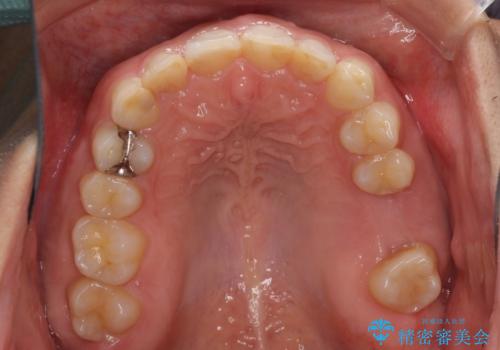

矯正治療とインプラント治療を同じ歯科医師が担当することで、通常見られるような複数医院を行き来する煩雑さや、複数担当医の見解の違いによる治療の遅滞といった煩わしさは一切なく、スムーズに治療を進めることができました。

安定して咬めるようになり、患者様には大変満足していただきました。